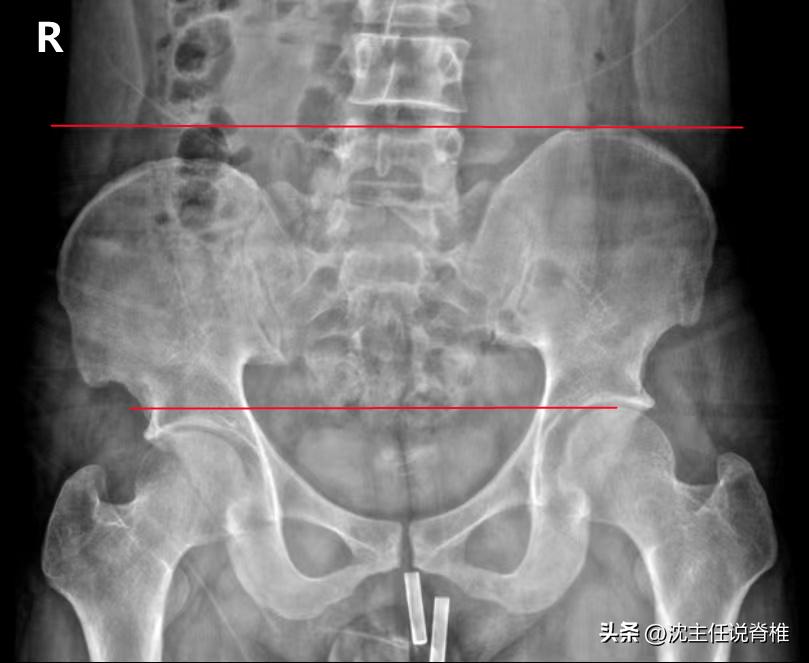

长短腿是一种常见的体态问题,如果您平时有 腰背疼痛、膝痛、踝痛 等症状,一定要注意进行长短腿的相关检查,否则疼痛不适的情况会反复出现。

如今,有越来越多报告显示,双下肢长度差距大于5mm的患者因 下肢力学不稳定 ,导致骨盆倾斜,附着在骨盆和腰部附近的肌肉出现不对称,容易引起髋关节和膝关节的 病变 ,甚至容易出现臀部或腰骶部疼痛。